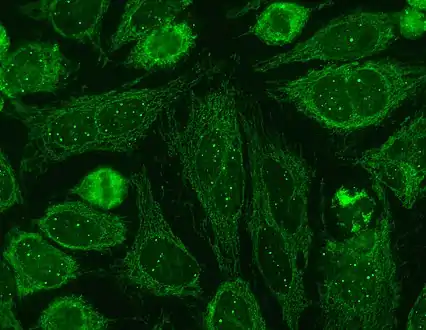

Intermediate-magnification micrograph of PBC showing bile duct inflammation and periductal granulomas, liver biopsy, H&E stain Immunofluorescence staining pattern of sp100 antibodies (nuclear dots) and antimitochondrial antibodies

Immunofluorescence staining pattern of sp100 antibodies (nuclear dots) and antimitochondrial antibodies

- Antimitochondrial antibodies are the characteristic serological marker for PBC, being found in 90–95% of patients and only 1% of controls. PBC patients have AMA against pyruvate dehydrogenase complex (PDC-E2), an enzyme complex that is found in the mitochondria.[11] Those people who are AMA negative but with disease similar to PBC have been found to have AMAs when more sensitive detection methods are employed.[13]

- Anti-np62[31] and anti-sp100 are also found in association with PBC.